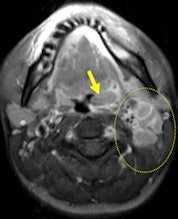

On MRI, oropharyngeal tularemia mostly presents with unilateral lymphadenopathy and associated oropharyngeal lymphoid tissue hypertrophy. A spectrum of homogeneous to inhomogeneous, and/or peripheral enhancement is parallel to development of central necrosis in the lymph nodes. Accompanying increased signal intensity occurs on T2-weighted images, and contrast enhancement of neighboring soft-tissue planes may be noted, especially in cases of suppuration. Restricted diffusion and an apparent diffusion coefficient (ADC) ranging from 0.5-1.05 mm/sn2 also are evident.

The main weakness of MRI is that its findings are nonspecific. Furthermore, both conventional MRI and diffusion-weighted imaging findings (ADC values) overlap with other granulomatous infections such as cat scratch disease and some malignant neoplasms such as squamous cell carcinoma, the researchers found.

Oropharyngeal tularemia should be considered in patients with a sore throat -- with or without an accompanying tender head and neck mass -- that does not respond to beta-lactam antibiotics and demonstrates necrotic lymphadenopathy and/or oropharyngeal lymphoid tissue hypertrophy with restricted diffusion in an MRI examination, particularly in endemic areas, they concluded.